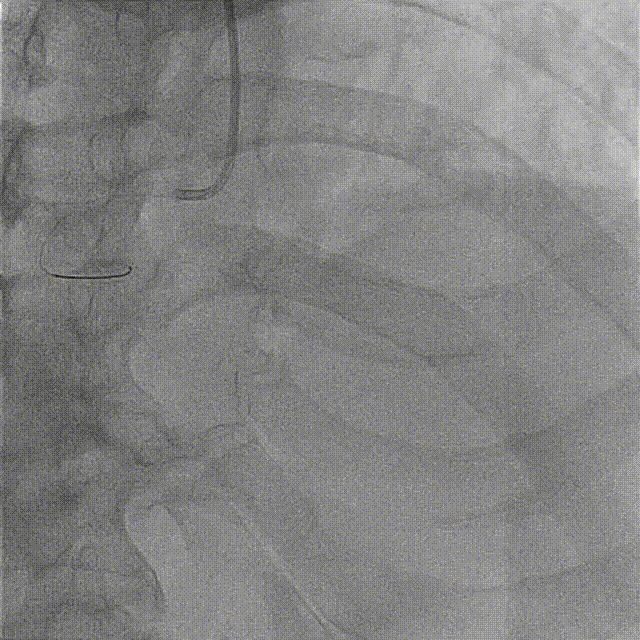

急性下壁心肌梗死诊断明确予以阿司匹林300mg+替格瑞洛180mg+阿托伐他汀40mg。入院后行急诊冠状动脉造影,结果显示,左冠未见明显狭窄,右冠中远段急性闭塞,可见血栓影。

导丝顺利通过闭塞段,但未见前向血流。

使用2.5*15mm球囊以6-8ATM压力预扩张。

预扩后右冠远端显影,远段及PD开口处可见血栓,抽吸出约2cm长血栓1条。

抽吸一次后PD血流好转,仍见血栓影,PL未见显影,再次抽吸。